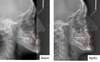

Monsieur G., 36 ans

Palais étroit, béance antérieure, encombrement bimaxillaire, "couloirs noirs" sur les cotés du sourire

Traitement :

- expansion maxillaire (disjonction maxillaire par appareil de Hyrax, durée : 4 mois) pour correction de l'inversé d'articulé bilatéral

- Gouttières d'alignement Invisalign (durée : 30 mois) pour fermeture de la béance et restauration d'une occlusion équilibrée (contacts postérieurs et antérieurs, guide antérieur fonctionnel). Embellissement du sourire grâce à l'alignement des dents et l'élargissement des arcades.